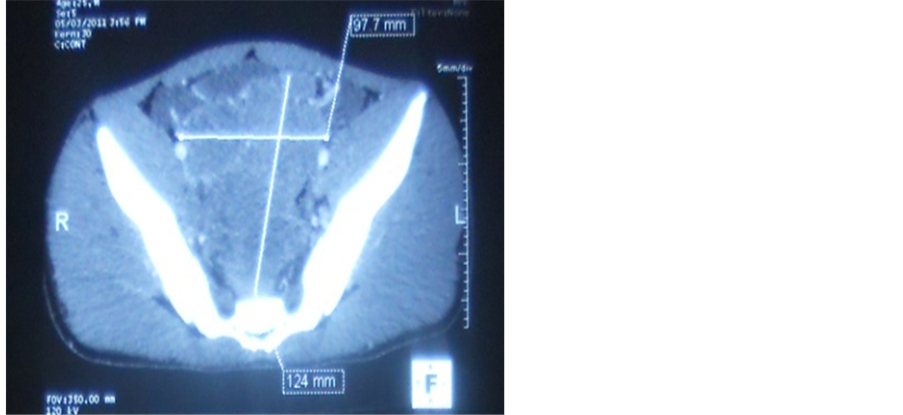

Radiography of the abdomen without preparation highlighted many water-scarce hydro levels. Testicular ultrasound highlighted an aspect of suspect heterogeneous testicle and bilateral testicular stones. A thoraco-abdominal-pelvic CT scan, there was the presence of 4 pulmonary nodules consistent with metastases, a bulky pelvic lymph node casting bridging the inter vesico-rectal area and responsible for extrinsic compression of the small intestine, lymph node inter casting aorto-caval and latero aortic and multiple hepatic secondary locations. Given this body of evidence, metastatic testicular tumor was raised (Figure 1 and Figure 2).

Figure 1. Pelvic lymph node casting.